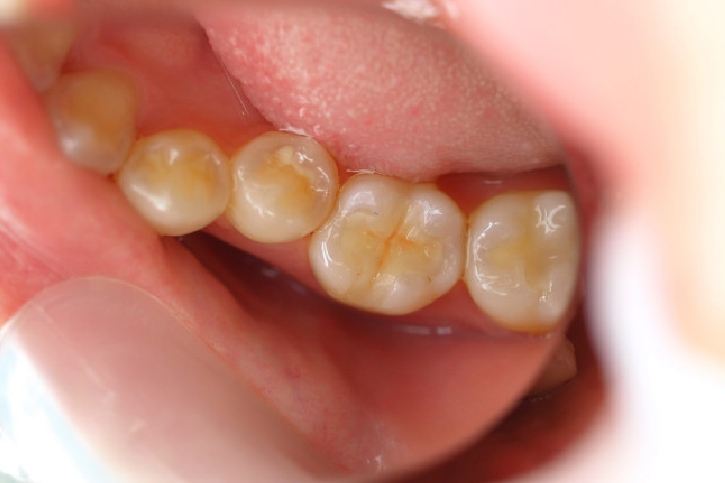

ハイブリッドセラミックス修復

担当歯科医師:丸林浩太郎

2013年3月2日千葉市中央区 S.K様 左下6番 ハイブリッドセラミックインレー修復